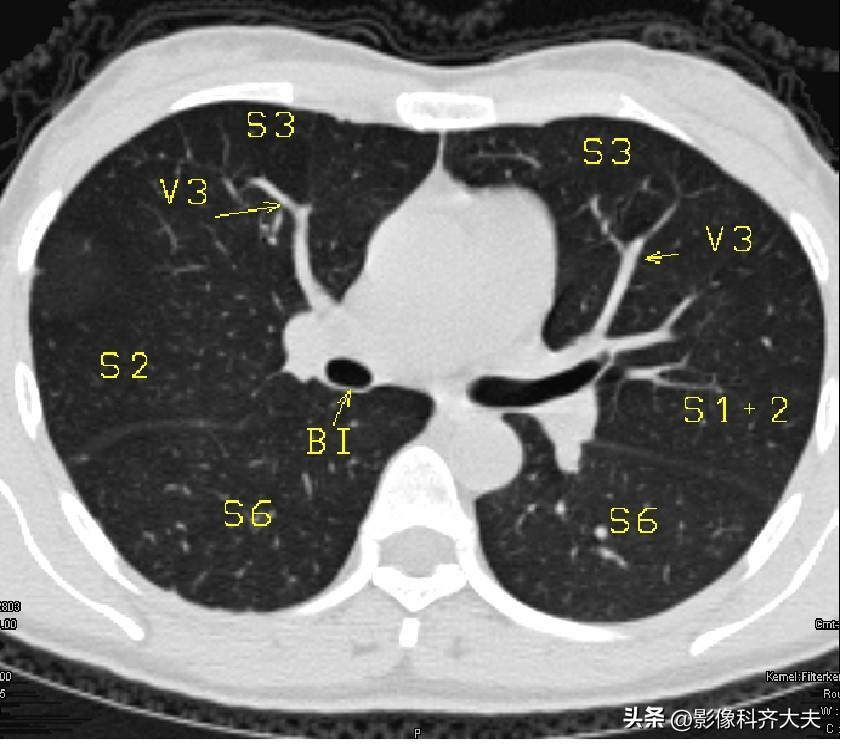

图9-隆突下2cm层面

▲V3:上叶前段静脉的段间支